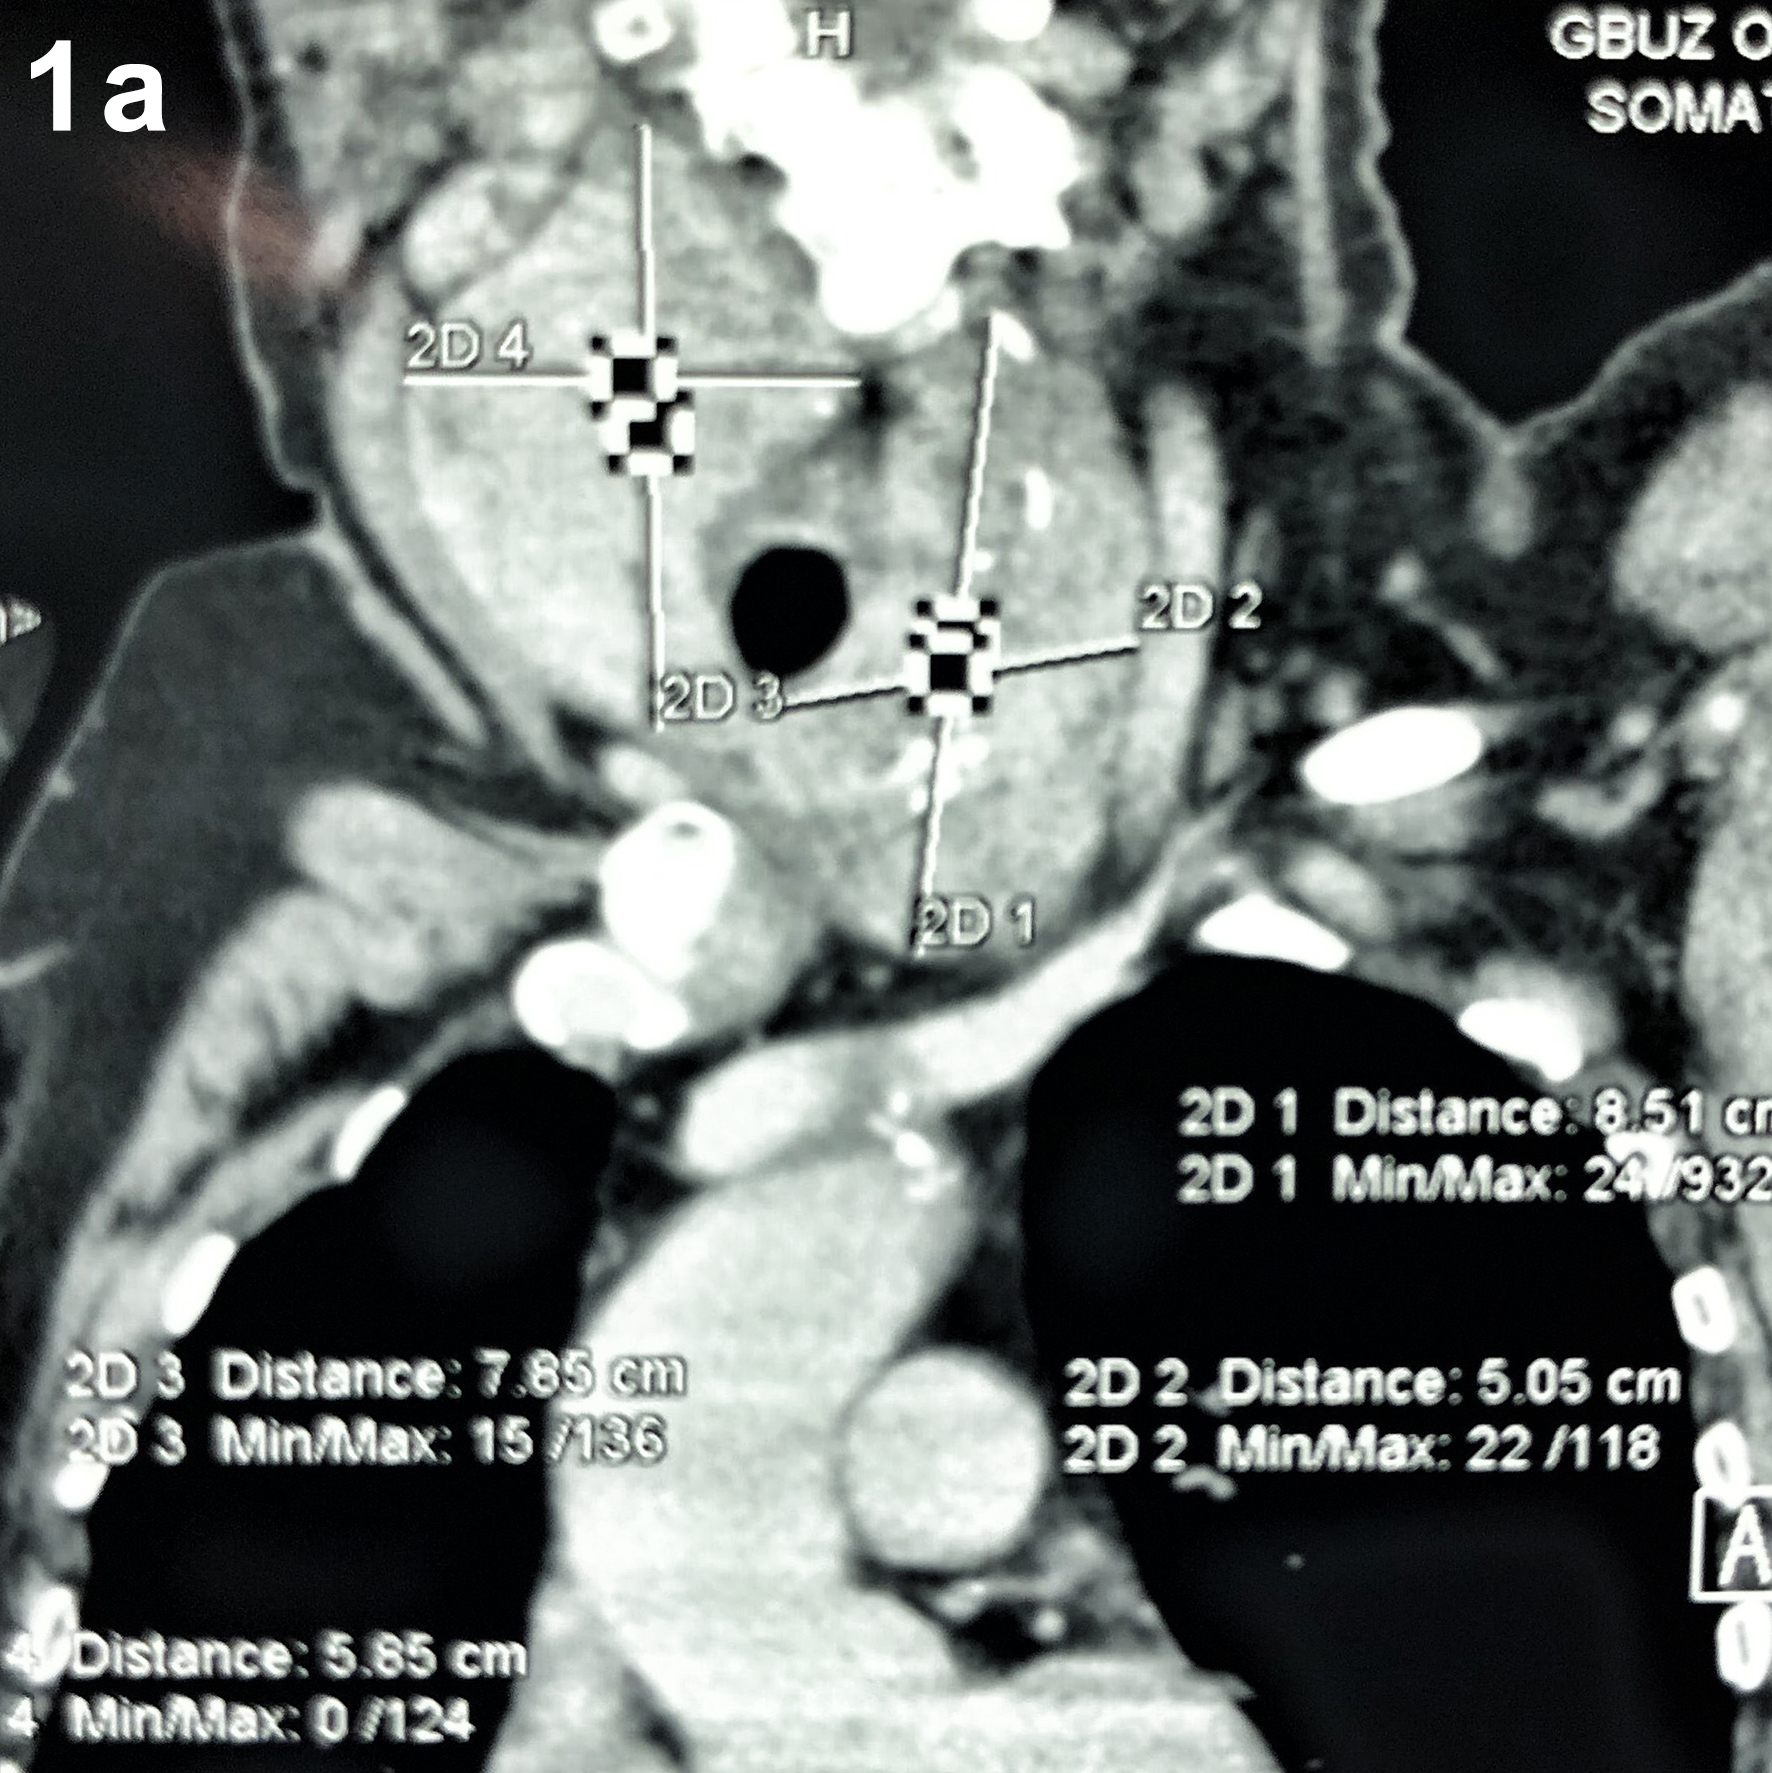

1. Рисунок 1a, b. Компьютерная томография шеи: диффузное увеличение щитовидной железы за счёт обеих долей с распространением загрудинно. Верхние полюса достигают сосцевидных отростков. Сужение просвета трахеи до 5 мм. | |

2. Рисунок 1a, b. Компьютерная томография шеи: диффузное увеличение щитовидной железы за счёт обеих долей с распространением загрудинно. Верхние полюса достигают сосцевидных отростков. Сужение просвета трахеи до 5 мм. | |